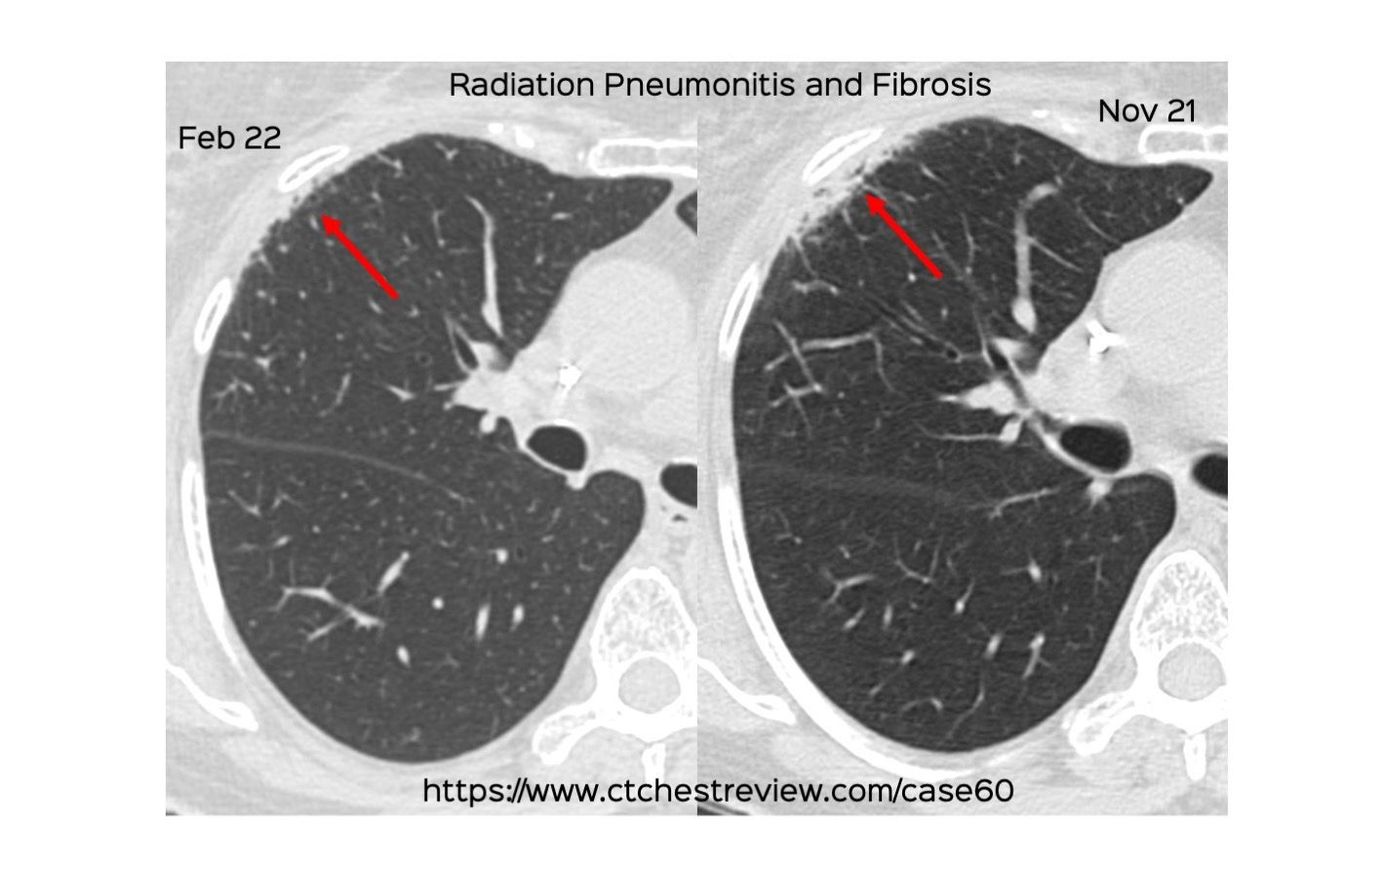

This 74-year old man presented with progressive perivertebral opacities recently. He had a history of radiation therapy for a spinal myeloma lesion in 2015. He had received CAR-T therapy for relapsed myeloma in Apr 2022.

The video discusses the concept of radiation recall pneumonitis in detail.